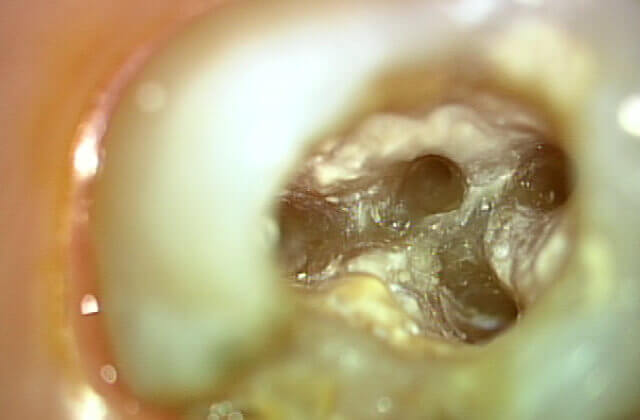

マイクロスコープで歯の内部を確認

(マイクロスコープを使うと歯の中に神経のある管が存在している事が分かります)